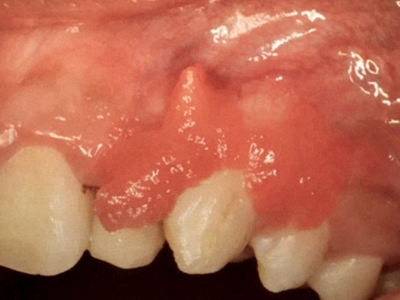

牙龈瘤是指发生在龈乳头部位的炎症反应性瘤样增生物,好发于女性,前磨牙区最为常见。牙龈瘤来源于牙周膜及牙龈的结缔组织,因其无肿瘤的生物学特征和结构,故非真性肿瘤,但切除后易复发,因此切除务必彻底,必要时拔除相关牙齿。

肿块有的有蒂,如息肉状;有的无蒂,基底宽广,生长较慢,但在女性妊娠期间可能迅速增大。较大的肿块可以遮盖一部分牙及牙槽突,表面可见牙压痕,易被咬伤而发生溃疡,伴发感染。随着肿块的增长,牙槽骨壁逐渐被破坏,牙可能发生松动、移位。

局部刺激因素,包括菌斑、牙石、食物嵌塞或不良修复体的刺激,引起局部长期慢性炎症,致使牙龈结缔组织形成反应性增生物,即牙龈瘤。此外,牙龈瘤可能和内分泌有关,妇女怀孕期间容易发生牙龈瘤,而分娩后会缩小或停止生长。